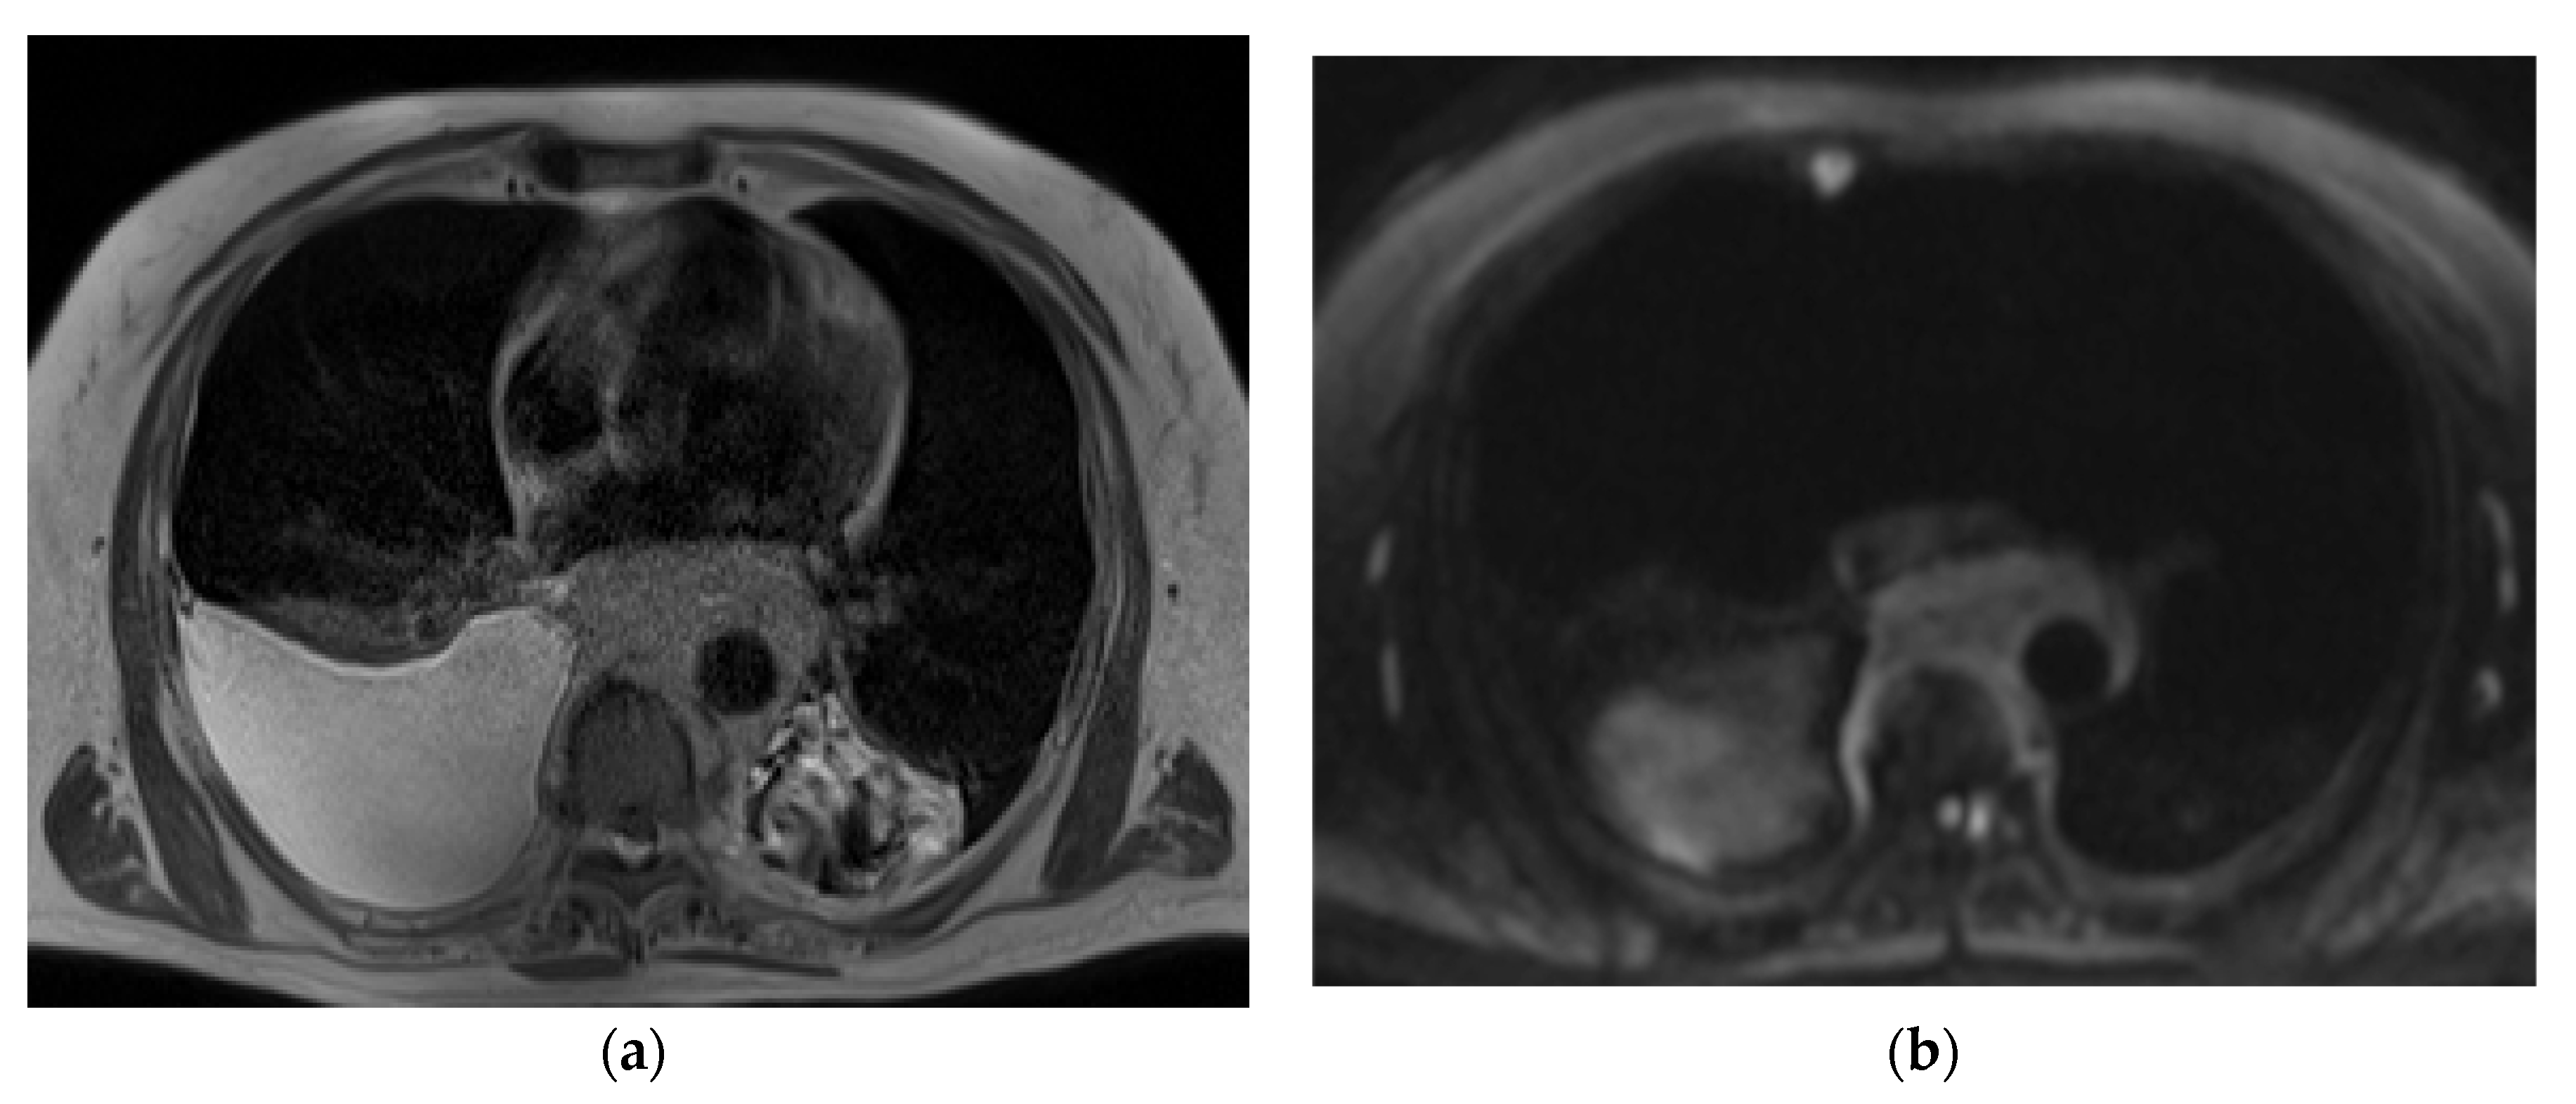

The representative T2-weighted images, DWI, and ADC maps of the malignant and benign lymph nodes are shown in Figure 2 and Figure 3 respectively.

Figure 3.

(a) T2-weighted axial MRI of 26-year-old female shows T2 heterogeneity in lymph nodes at subcarinal location (station 7); (b) Diffusion-weighted axial MRI shows mild central diffusion restriction; (c) Systemgenerated ADC map of corresponding lymph node shows ADC mean value of 1.501 × 10−3 mm2/s. The final pathological diagnosis was tuberculosis.